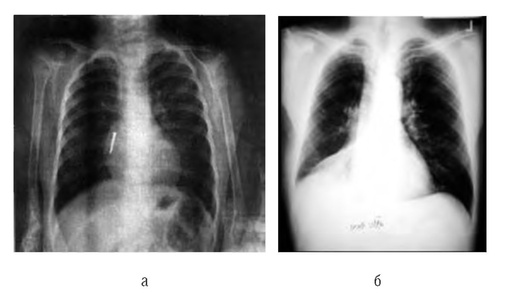

Дополнительный метод диагностики - рентгенография шейного отдела в переднезадней и латеральной проекциях (рис. 3-2). Проведение исследования - иногда причина отсрочки восстановления проходимости дыхательных путей. Рентгенографию необходимо выполнять только при сомнительном диагнозе и при сопровождении ребенка врачом, владеющим методикой интубации. Рентгенографию производят в вертикальном положении ребенка. Не следует пытаться получить рентгенограммы у больных с тяжелыми расстройствами дыхания. Диагностические признаки - тень надгортанника при увеличенном объеме набухшей мягкой ткани и, что более важно, округленный и утолщенный край черпалонадгортанных складок (положительный «симптом большого пальца»). Однако отрицательные данные рентгенографии не исключают эпиглоттит, особенно в ранней стадии. Для диагностики рекомендуют использовать ультразвуковое исследование (УЗИ).

image

Рис. 3-2. Рентгенологическая картина при эпиглоттите: а - норма; б - симптом большого пальца